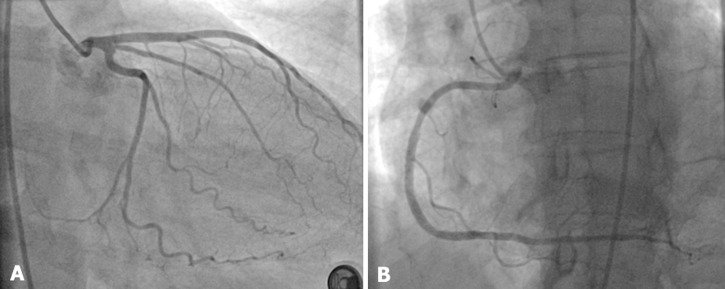

Follow-up and outcome of interventions: after a three-month follow-up, the patient remained free of symptoms, and a control coronary angiogram showed the disappearance of the SCAD in the Cx artery and patent stents in the RCA artery (Figure 4).

Figure 4.

control coronary angiogram showing the disappearance of the circumflex dissection with smooth coronary arteries (A) and the patency of the right coronary artery stents (B)